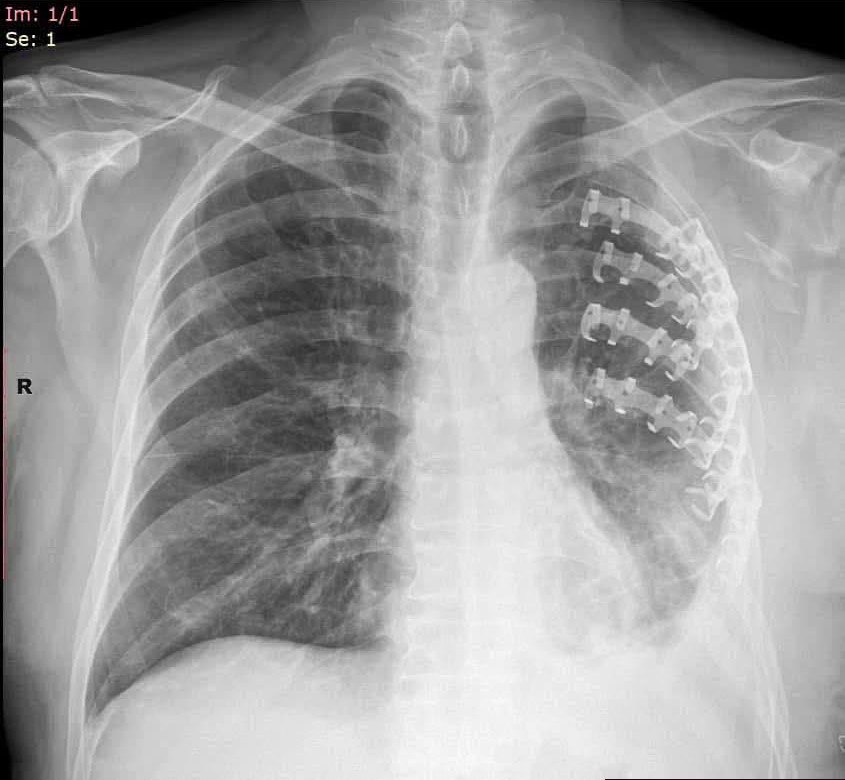

Гэмтэл согог судлалын үндэсний төвийн Хавсарсан гэмтлийн мэс заслын тасгийн эмч, мэргэжилтнүүд цээжний хөндийн битүү гэмтэл болон дурангийн мэс засал, олон хавирганы тогтворгүй хугарлыг бэхлэх эмчилгээг эх орондоо нутагшуулан, эмнэлгийн тусламж үйлчилгээнд өдгөө 7 дахь жилдээ хэрэгжүүлэн ажиллаж байна.

Уг ажлын үр дүнд Сүхбаатар, Өмнөговь, Дорноговь, Хэнтий, Говь-Алтай, Булган аймгийн эмнэлэгт цээжний хөндийн битүү гэмтэл болон дурангийн мэс засал, хавирганы хугарлыг бэхлэх эмчилгээ хийж эхэлснээр орон нутгийн иргэдэд цаг алдалгүй тусламж үйлчилгээ үзүүлж, лавлагаа шатлалын эрүүл мэндийн байгууллагын ачаалал, төвлөрлийг сааруулахад чухал ач холбогдолтой ажил болсон билээ.